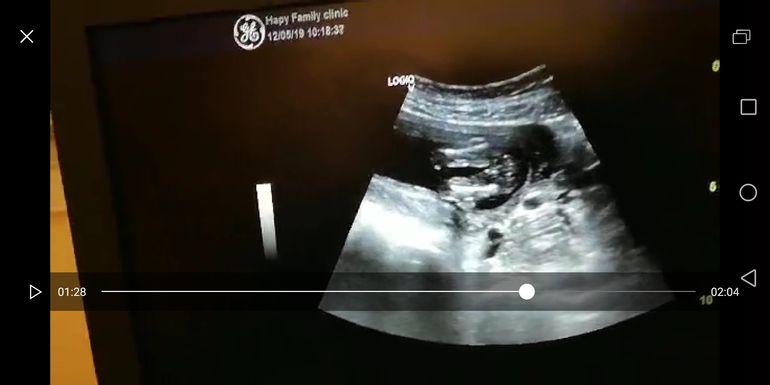

УЗИ в 16 недель, пол плода

Результаты: УЗИ, КТГ, доплера, скринингаДевушки, посмотрите, пожалуйста. Сделали узи, не дождавшись скрининга. Сказали девочка. Но по всем ощущениям и по большому нашему желаю мальчик... Хотя я понимаю, что вероятность ошибки мала. Ну а вдруг спряталась мошонка? Первая дочь, наша любимая и желанная.

нам еще на 1 скрининге сказали и дали 90%, на этой неделе только подтвердили. Но узист и аппаратура экспертного класса. Ошибаются, конечно, но от слепоты, наверное, там прям показывали все уже.

Это девочка, с такого ракурса яйчишки хорошо видать и прятаться им там негде🙂